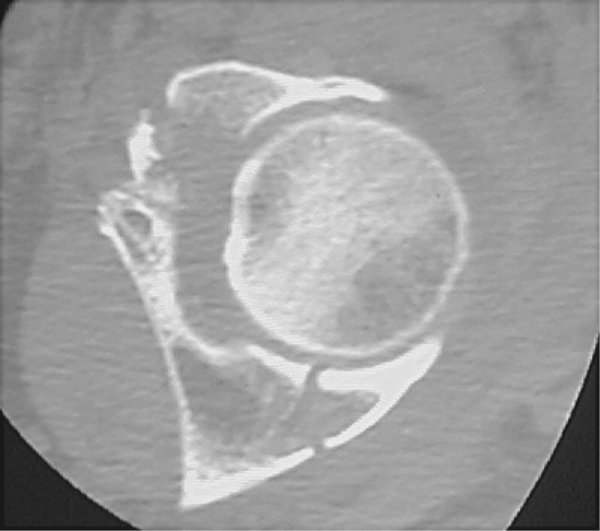

Return to Acetabular Fracture